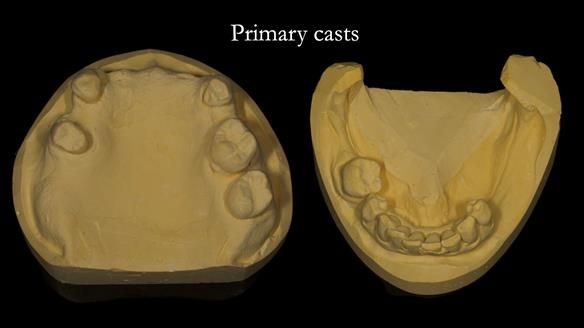

In this edition, I present the removable partial denture treatment for Jean, an 80-year-old woman with a sore mouth caused by a soft tissue-supported 'gum stripper' acrylic denture and a clenching habit. Below, I outline the step-by-step process of her treatment. It wasn't straightforward; I had to remake the denture after it fractured to achieve a satisfactory result. Each patient is unique, and sometimes a new RPD serves as a prototype. Occasionally, I need to make adjustments, learn from any mistakes, and refine the design to get it right.